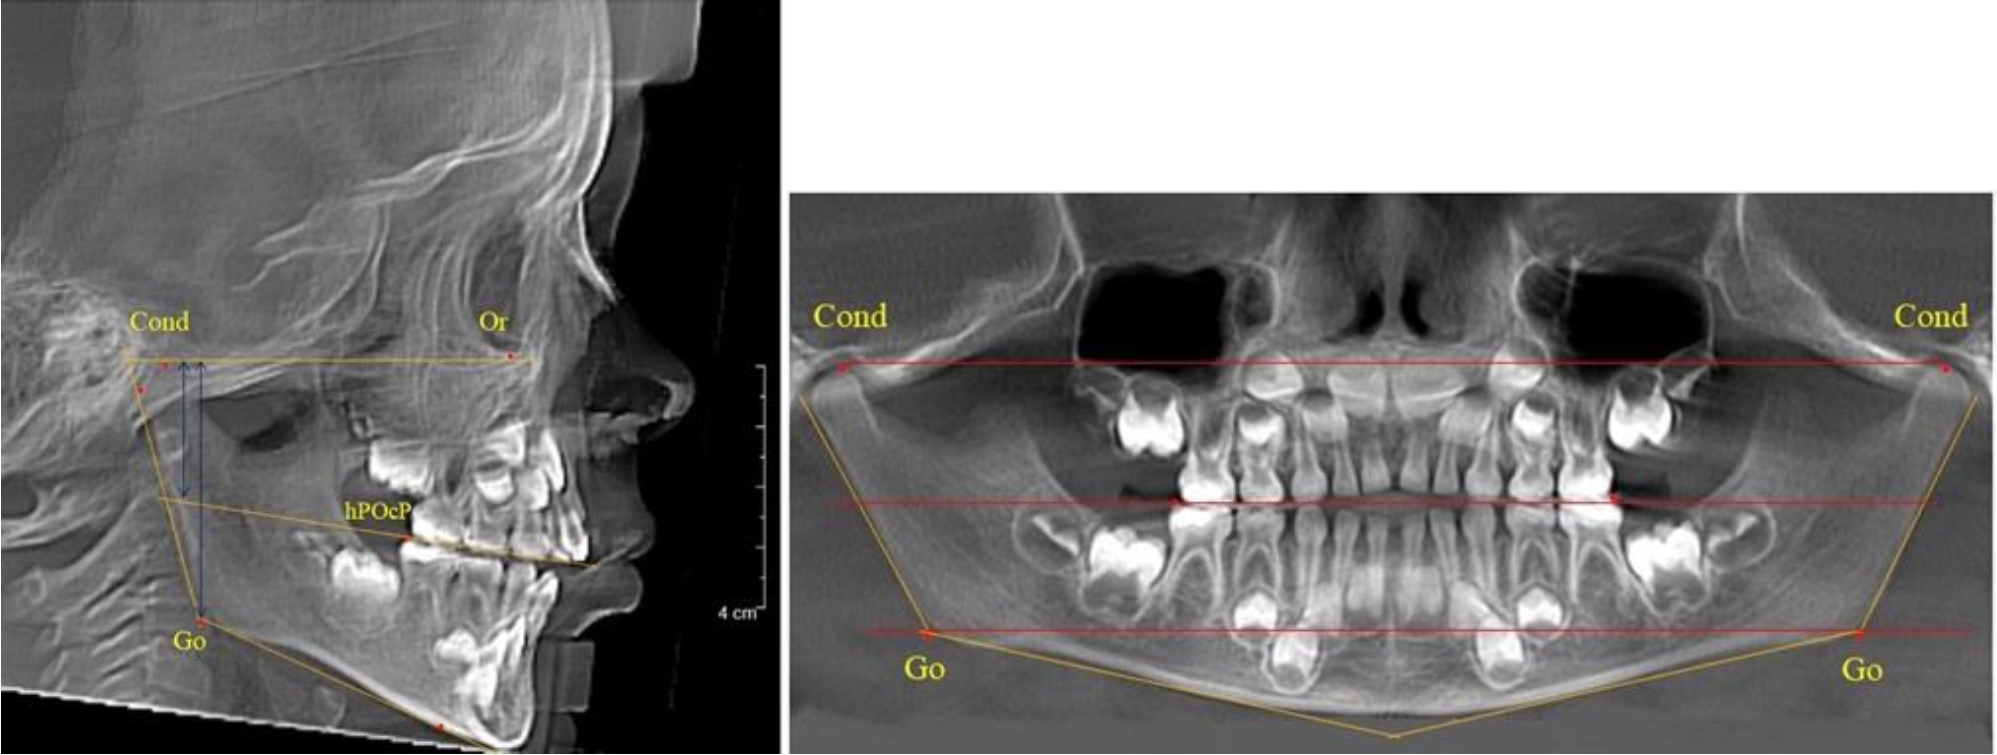

В 1-й группе были проанализированы 7 телерентгенограмм и 7 ортопантомограмм, что составило (6,60 ± 2,41) % от числа изученных рентгенограмм. На всех парах рентгенограмм угол нижней челюсти, измеренный на телерентгенограмме, соответствовал углу, полученному при построении угла на ортопантомограмме. Окклюзионная линия практически однотипно делила ветвь на два отдела (рис. 1).

Как на ортопантомограмме, так и на телерентгенограмме высота ветви у детей в периоде сформированного прикуса молочных зубов составляла (42,21 ± 2,48) мм. При этом высота верхней окклюзионно-суставной части была (22,57 ± 1,46) мм, а нижней – (19,64 ± 1,54) мм.

Учитывая вариабельность абсолютных величин, определи относительные показатели соразмерности частей ветви нижней челюсти. Так, отношение высоты верхней части ветви к нижней в среднем составляло 1,15 ± 0,13. Отношение общей высоты ветви к верхней ее части составляло 1,87 ± 0,14, а отношение общей высоты ветви к нижней ее части было 2,14 ± 0,16 и достоверных различий по относительному показателю отношения всей высоты к верхней и нижней челюсти нами не отмечено (р ˃ 0,05). При этом визуально обе части выглядели примерно равноразмерными.

Рис. 1. ТРГ и ОПТГ пациента 1-й группы